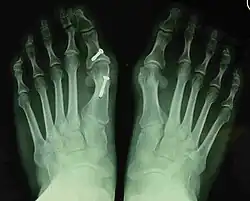

- Second metatarsal stress fracture (Fig. 5)

- Over-correction (Fig. 6)